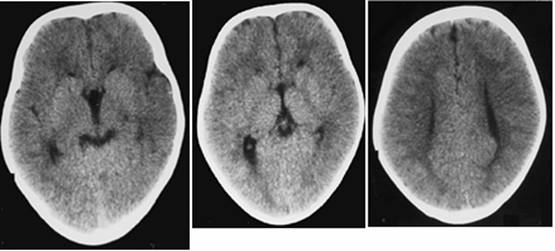

Figure 5

Clinical and image aspects of patient 5

Int J Med Sci Image

Figure 6

Clinical and image aspects of patient 6